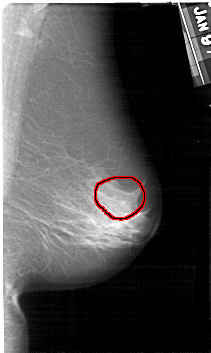

A_1378_1.LEFT_CC

LEFT_CC LINES 5281 PIXELS_PER_LINE 2701 BITS_PER_PIXEL 12 RESOLUTION 43.5 OVERLAY

FILE: A_1378_1.LEFT_CC.OVERLAY

TOTAL_ABNORMALITIES 1

ABNORMALITY 1

LESION_TYPE CALCIFICATION TYPE PLEOMORPHIC DISTRIBUTION CLUSTERED

ASSESSMENT 4

SUBTLETY 4

PATHOLOGY BENIGN

TOTAL_OUTLINES 1

BOUNDARY